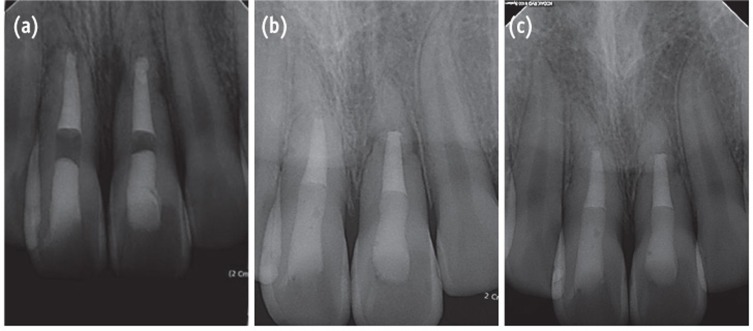

Four weeks after the trauma, a radiolucent area appeared intra-canally on the apical portion of the coronal fragment and it continued to progress until 6 weeks of observation (Figures 1b and 1c). Root canal treatment was initiated on the coronal fragment with K-file and irrigated with 5% sodium hypochlorite. Working length was established with an apex locator (DentaPort ZX, Morita, Kyoto, Japan). Special care was taken to instrument within the coronal fragment. After 2 months of intracanal calcium hydroxide dressing, the canal was obturated with mineral trioxide aggregate (MTA, ProRoot, Dentsply, Tulsa, OK, USA) (Figure 2a).

At the 2-year follow-up evaluation, the patient did not report any clinical symptoms. Complete healing of the root fracture with the interposition of hard tissue between the fragments was observed on the periapical radiographs (Figure 2c).

Andreasen and Hjorting-Hansen classified the healing of root-fractured teeth into four groups, (1) healing with hard tissue, (2) healing with the interposition of hard and soft tissue, (3) healing with interposition of soft tissue, and (4) no healing.12 The factors influencing the healing of a root-fractured tooth include the patient's age, stage of root growth, mobility of the coronal fragment, and diastasis of the fragments.1 In the present patients, injury factors (e.g., fragment diastasis and mobility of the coronal fragment) exerted a strong influence on healing at the fracture line and on pulpal necrosis. Case 1 had small diastasis of less than 0.5 mm and no mobility, and the tooth healed with hard tissue and with the evidence of a spontaneous healing process such as ISR. Case 2 showed extrusive luxation of the crown fragment with a large amount of diastases. It was impossible to determine whether the pulp was vital because root canal treatment had been already initiated by the emergency dentist. The follow-up radiographs showed healing with hard and soft tissue. Case 3 showed lateral luxation of the crown fragment with a large amount of diastases. Interposition of soft tissue with pulp necrosis of coronal fragment was also observed. Increasing diastases between fragments reportedly increases the risk of pulp necrosis, and decreases the likelihood of hard tissue healing.13 According to a report, the frequency of pulp necrosis is stable with diastasis of up to 1 mm, whereas hard tissue healing shows stable values up to 0.5 mm.13

Figure 2

Radiograph of the tooth. (a) After root canal treatment; (b) At the 1-year follow-up evaluation; (c) At the 2-year follow-up evaluation. 2-year follow-up radiograph reveals healing with the interposition of hard tissue between the fragments.